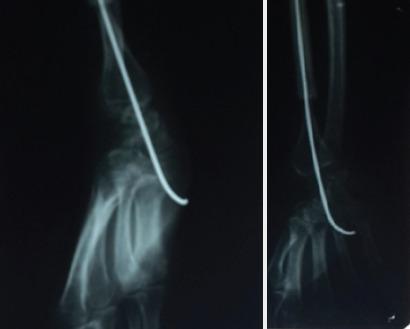

A 40-year-old female was diagnosed with Campanacci Type 3 GCT-DER 7-year back. The patient was operated and treated by excision of tumor and reconstruction with contralateral fibular grafting with K-wire fixation of DER7-year back and biopsy of growth was sent. After 7 years, the patient again developed swelling over the right wrist and radiological diagnosis of GCT Campanacci Grade 3 is made. She is managed by resection of tumor tissue by volar approach to DER with proximal row carpectomy with ulnocarpal fusion with retrograde K-wire fixation of the 3rd metacarpal resulting in centralization of ulna.

一名40岁女性7年前被诊断为坎帕纳奇3型桡骨远端骨巨细胞瘤。患者接受了手术,手术方式为切除肿瘤并采用对侧腓骨移植重建,同时用克氏针固定桡骨远端,术后7年送检生长组织活检。7年后,患者右腕再次出现肿胀,经放射学诊断为坎帕纳奇3级骨巨细胞瘤。通过掌侧入路切除桡骨远端肿瘤组织,近端排腕骨切除术,尺腕融合术,同时对第三掌骨进行逆行克氏针固定,使尺骨中心化,以此对患者进行治疗。